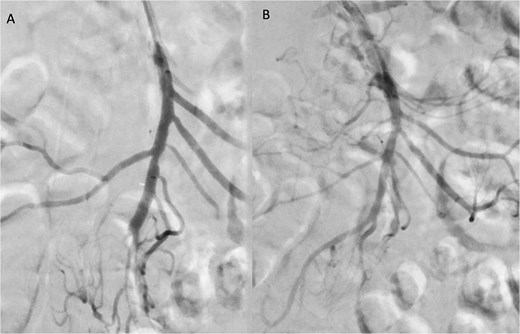

A 76-year-old female patient with a medical history of diabetes mellitus and cholecystectomy presented to the emergency department with a 7-month history of postprandial abdominal pain, food fear, and weight loss (25–30 kg). Over the past 3 days she referred symptom worsening to constant pain. On the physical examination, the abdomen was tender to palpation. Laboratory results revealed leukocytosis (13.700/μl), high C-reactive protein (23 mg/dl) and lactate 0.7 mmol/L. A previously performed computed tomography angiography (CTA) in context of a lithiasic cholecystitis revealed celiac trunk occlusion and pre-occlusive stenosis of the SMA ostium but the patient was not referred for a vascular surgery consultation. A CTA scan obtained in the emergency department revealed thrombotic occlusion of the SMA origin associated with distal embolization (Fig. 1A–C). In this context, the diagnosis of acute-on-chronic mesenteric ischemia was assumed, and the patient was proposed for urgent endovascular revascularization. A 7F (French) sheath was placed via percutaneous access in the left brachial artery, and SMA catheterization was performed using a triaxial system (sheath, MP catheter and Progreat® catheter). Diagnostic angiography confirmed the CT findings (Fig. 2A). Catheter-directed thrombolysis was first performed with a 5 ml bolus of alteplase, followed by percutaneous thrombectomy using the Penumbra® system (Fig. 2B), with retrieval of fresh thrombus (Fig. 3). Primary stenting of the SMA ostium was also performed using an Advanta® 6 × 39 mm stent with proximal flair, with an excellent imagological result (Fig. 4A and B). The postoperative course was uneventful, with significant improvement of symptoms and clinical status. A CTA prior to discharge revealed a patent stent with proper placement and no evidence of residual thrombus (Fig. 5A and B). The patient was discharged on the seventh postoperative day with apixaban 5 mg twice daily. Follow-up of the patient at 6 months revealed that the stent remained patent, with no reported abdominal complaints. The patient gained 15 kg at this point of follow-up.

Pre-discharge follow-up CTA showing patent SMA and no complications, with coronal (A) and sagittal (B) images.